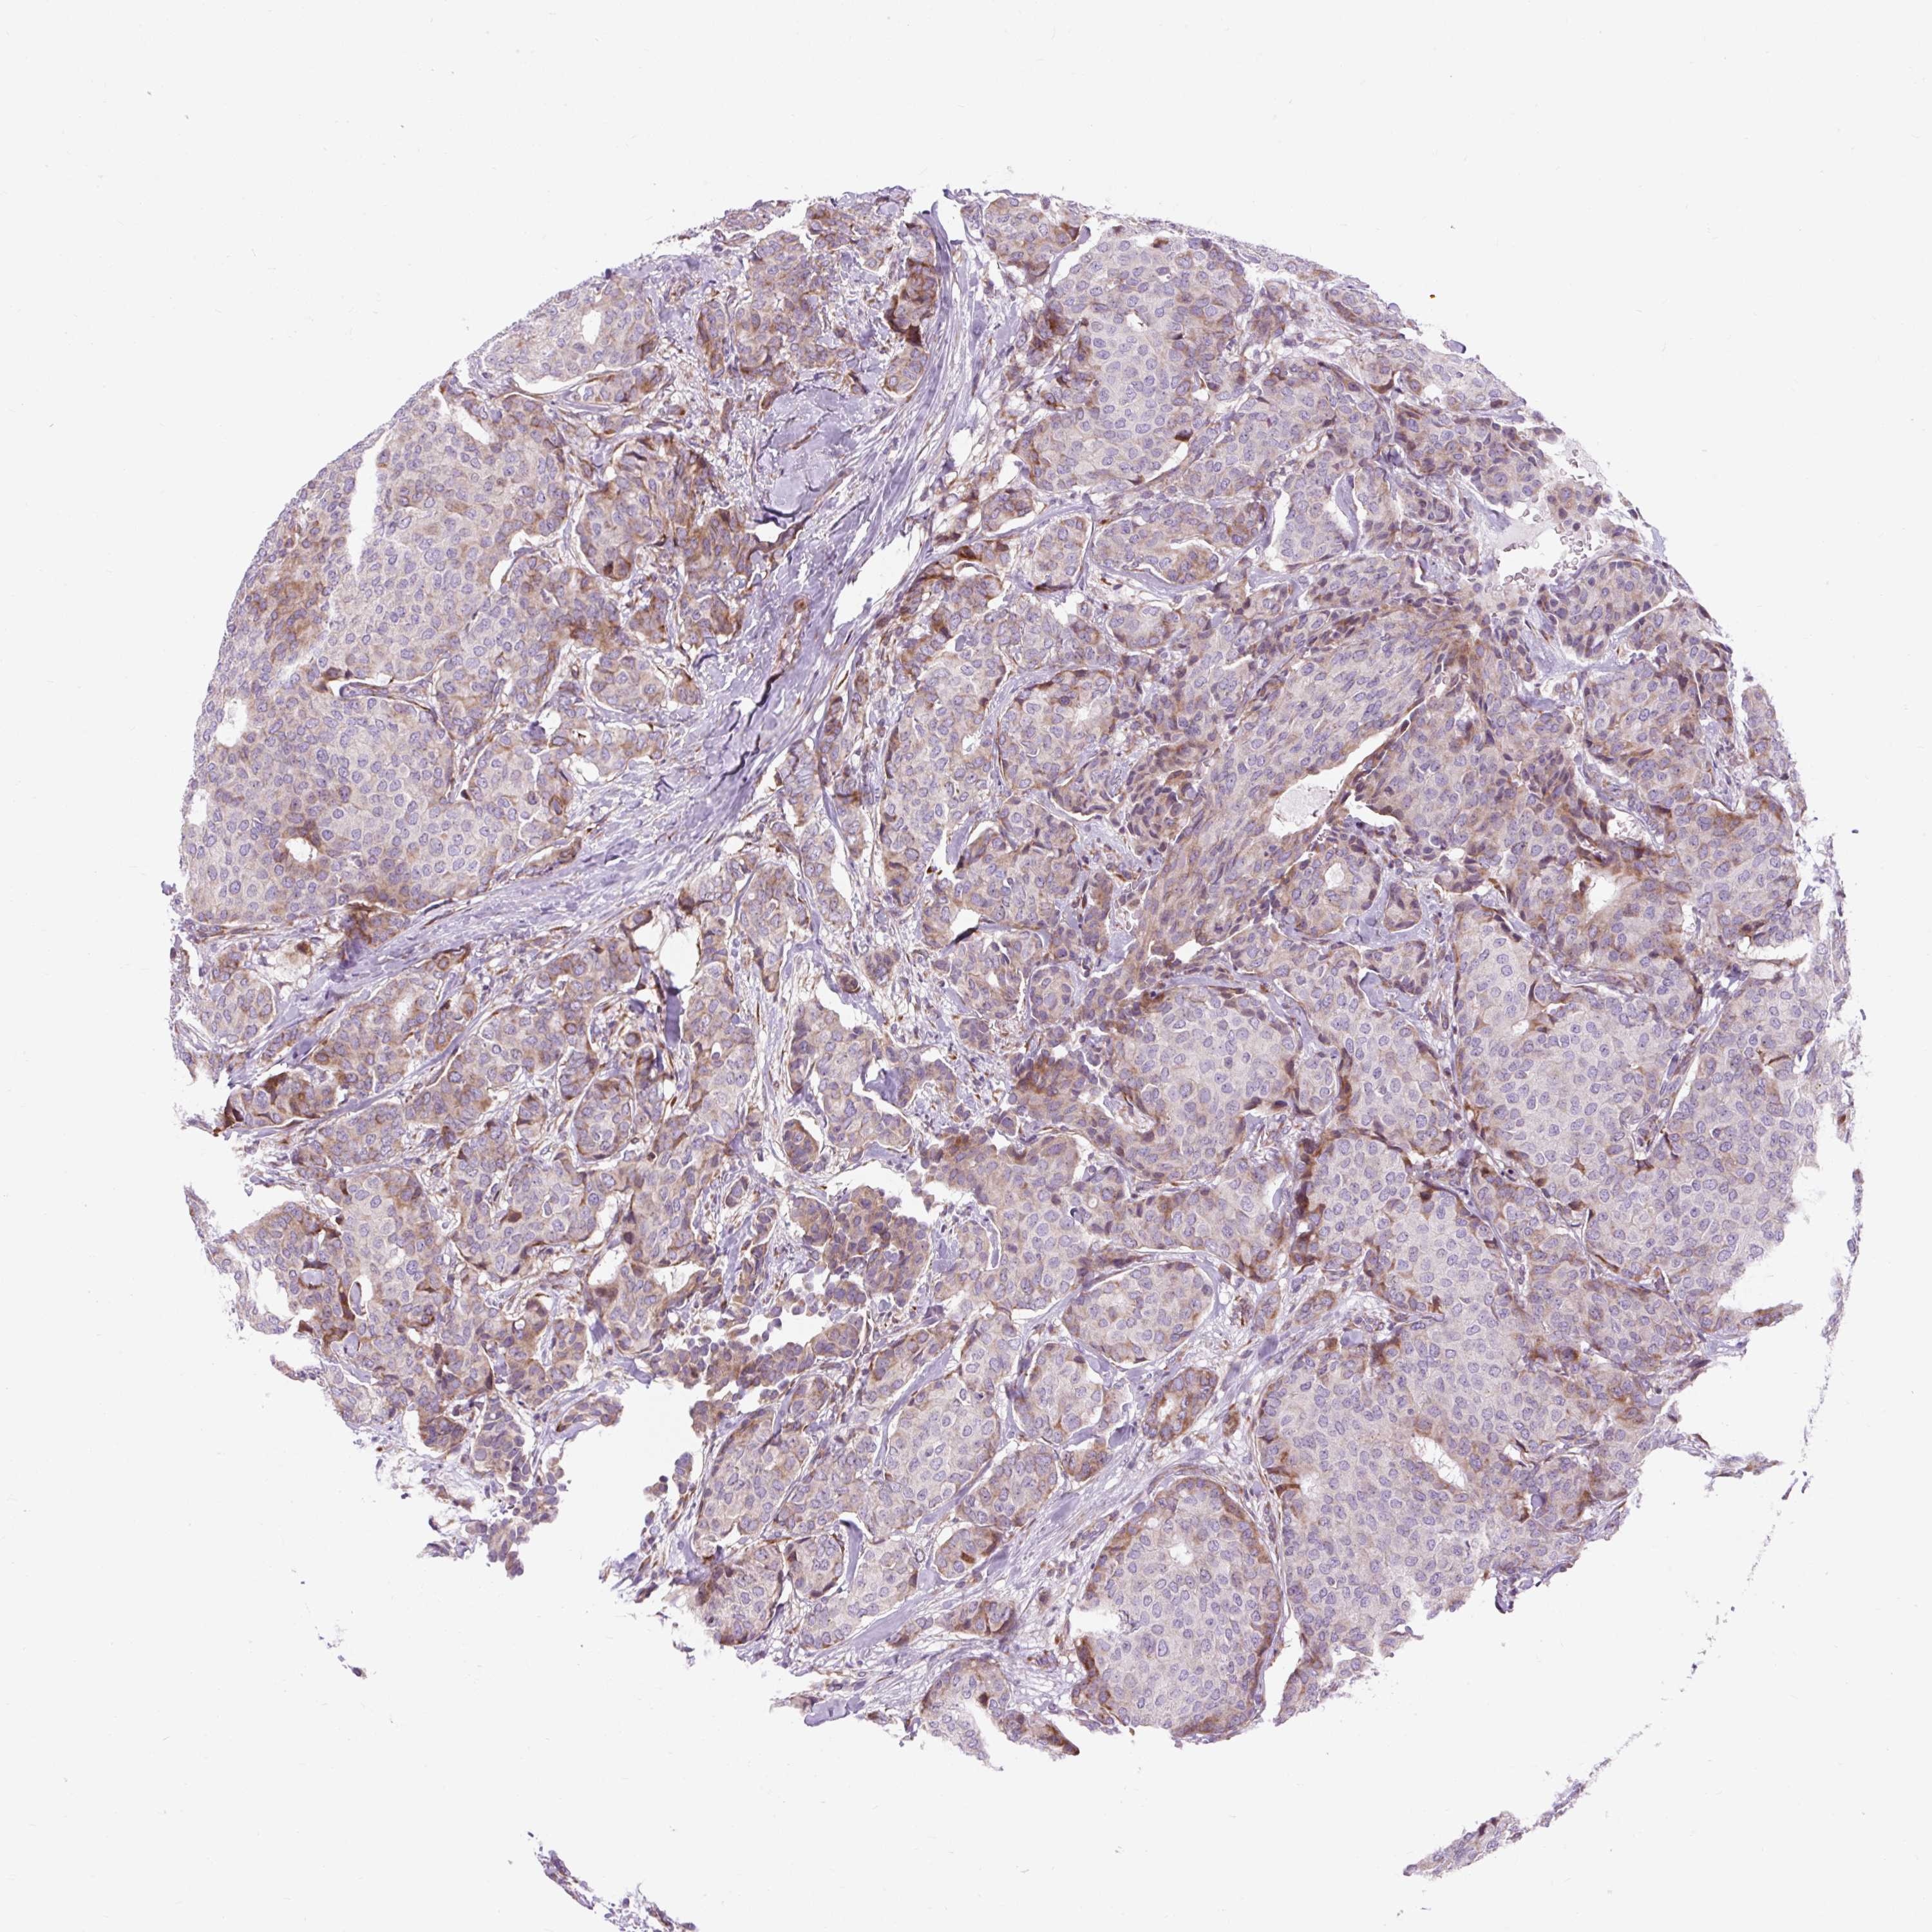

CANCER BREAST CANCER Show tissue menu

BRCA TCGA BRCA VALIDATION PROTEIN EXPRESSION

Breast cancer

Human cancer

Breast invasive carcinoma